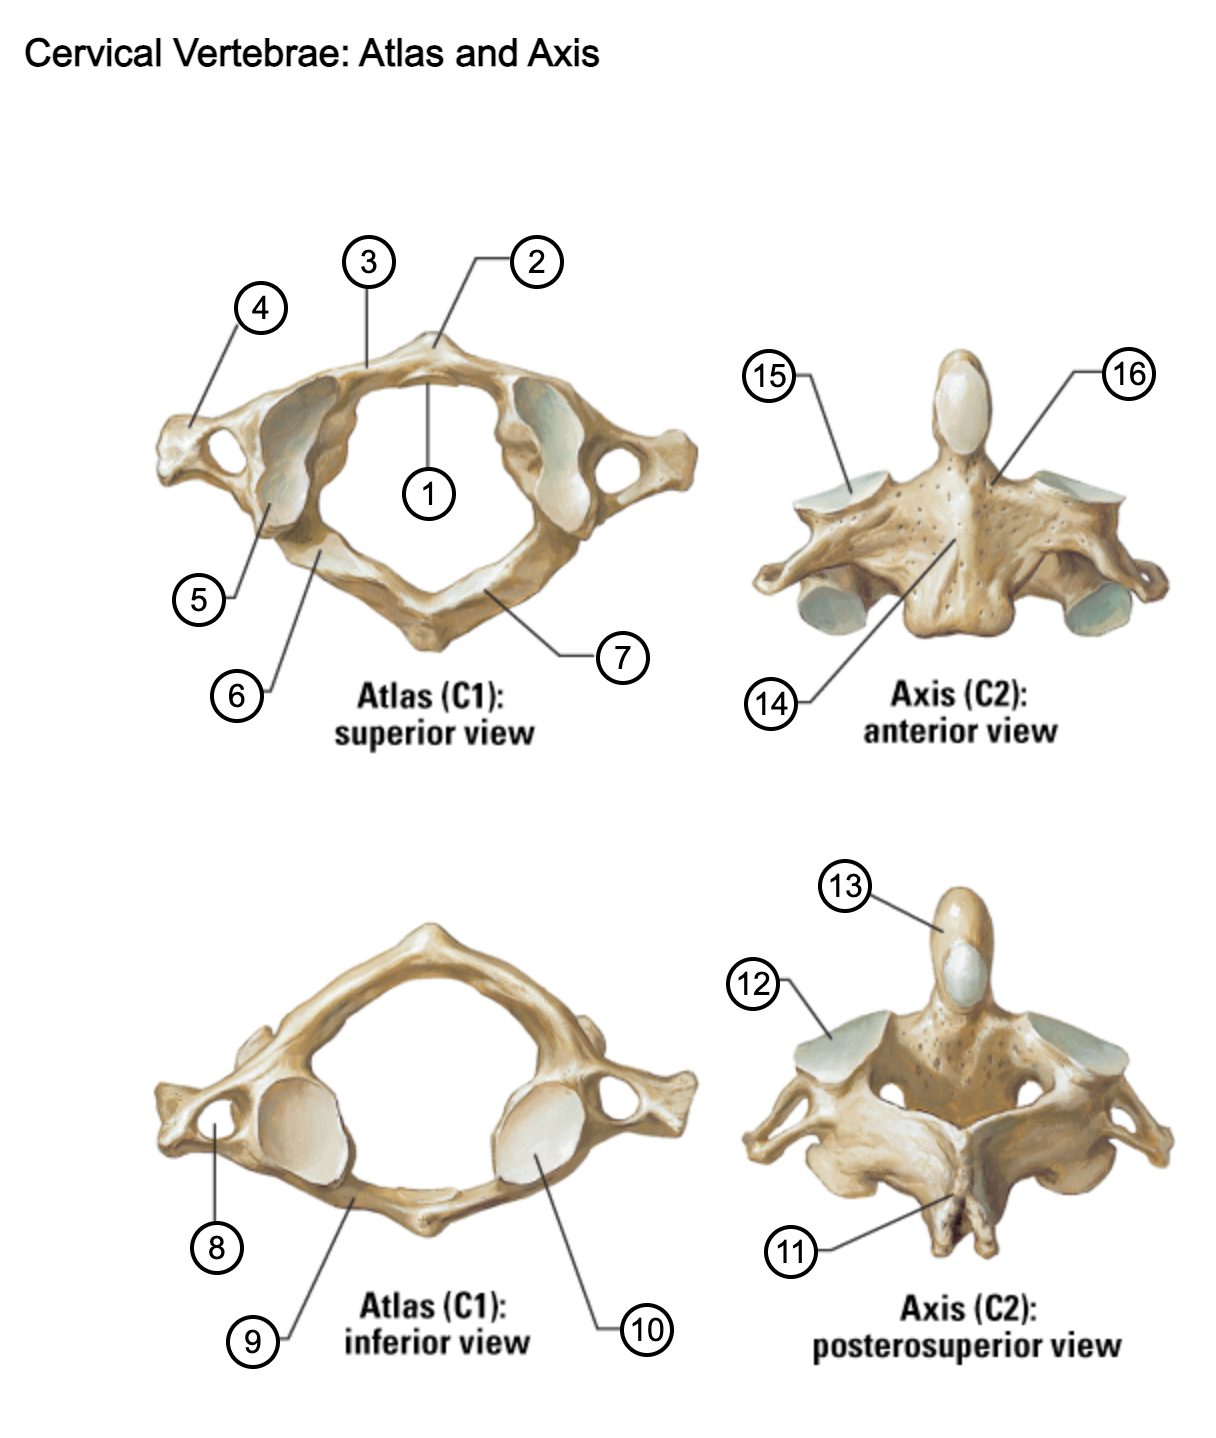

1

facet for dens

2

anterior tubercle

3

anterior arch

4

transverse process

5

superior articular surface of atlas

6

groove for vertebral artery

7

posterior arch

8

transverse foramen

9

anterior arch

10

inferior articular surface of atlas

11

spinous process

12

superior articular facet

13

dens of axis

14

body of axis

15

superior articular facet for atlas

16

pedicle of vertebral arch